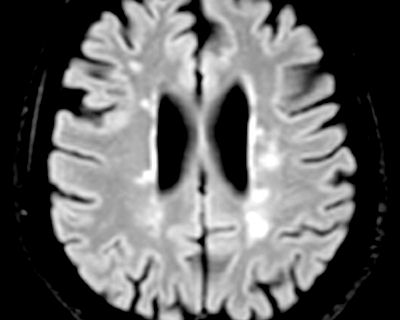

typical MS lesions typical vascular lesion lesion not typical for MS nor vascular a mix of vascular and MS lesions